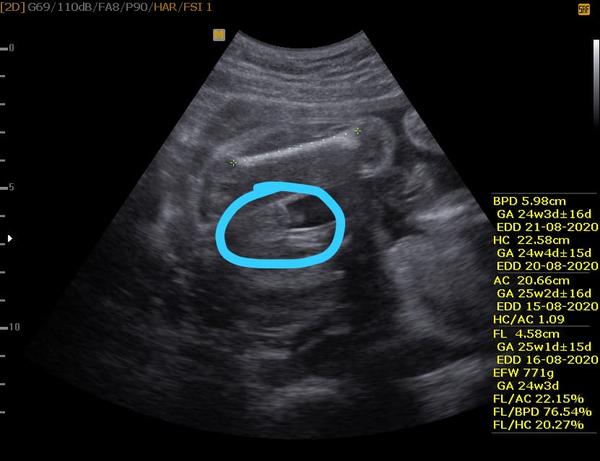

Je to holka nebo kluk? Nejistota po vyšetření ultrazvukem.

ahoj holky co vidíte jsem v 20 tt. v 16 týdnů mi můj gynekolog rekl vidí na 85 procent kluka a dnes gynekolozka řekla ze vidí zase holku dneska to je 20 týden